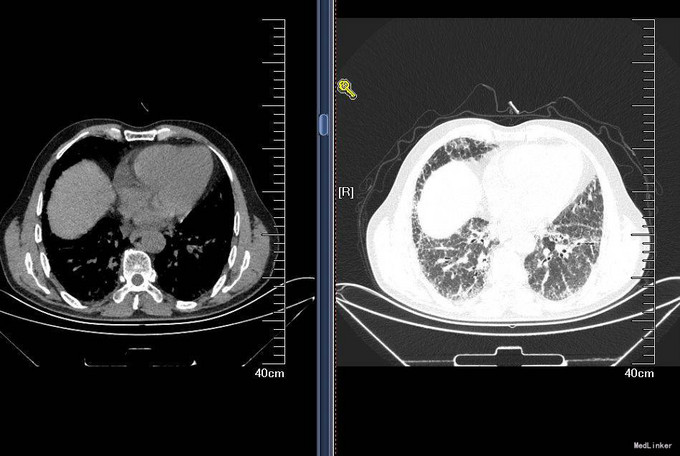

查体:T36.5℃,P 80次/分,R 18次/分,BP 120/80mmHg,神清语明,查体合作,周身皮肤无黄染及出血点。巩膜无黄染,结膜无苍白,球结膜无水肿,口唇无发绀,颈静脉无充盈,颈部浅表淋巴结未触及。双肺呼吸音粗,未闻及干湿性啰音,心音钝,律齐,各瓣膜听诊区未闻及病理性杂音。腹平软,无压痛,无反跳痛及肌紧张,未触及包块。肝肋下未触及,双肾区无扣痛,移动性浊音阴性。双下肢无水肿。 入院后完善肝肾功离子,血气分析,血常规,CRP,支原体抗体,肺通气功能,弥散功能等检查,检验回报:血常规:白细胞计数 9.710^9/L;中性粒细胞百分比 46.8%;红细胞计数 4.6810^12/L;血红蛋白 148g/L;血小板计数 21310^9/L;CRP:C-反应蛋白 <3.28mg/L;肺炎支原体抗体:肺炎支原体抗体 阴性(-); 肺通气功能:FEV1/FVC:90,%Pre:78%,混合性通气功能障碍,以限制为主;支气管舒张试验试验:支气管舒张试验阴性,FEV1改善率1%,增加30ml;弥散功能:总弥散量中度下降,单位弥散量正常;胸部HRCT:双肺弥漫性间质性肺炎。 双侧胸膜局部增厚。